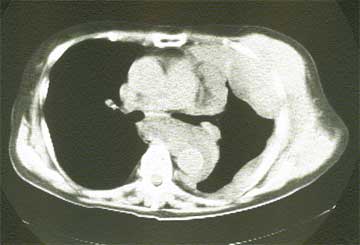

(写真 悪性胸膜中皮腫CT像)